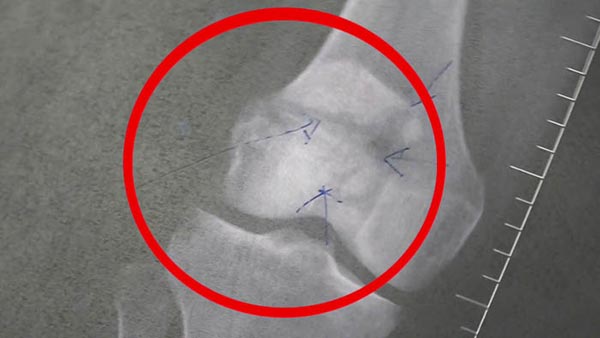

โดยหลังจากตรวจบาดแผลและอาการบาดเจ็บของคนไข้ ซึ่งอาการน่าเป็นห่วงตรงจุดบาดแผลที่หัวเข่าเปิด กระดูกสะบ้าข้างขวาหัก ประกอบกับแผลถูกแช่น้ำกว่า 2 วัน เสี่ยงบาดแผลติดเชื้อ เบื้องต้นจะต้องเข้าห้องผ่าตัดทำการล้างแผลให้ปลอดเชื้อก่อน และจะต้องฉีดยาฆ่าเชื้อ 14 วัน เมื่อแผลปลอดเชื้อแล้วก็จะผ่าตัดอีกครั้งหนึ่ง

ด้าน นพ.ธีระศักดิ์ วิริยานนท์ ผู้อำนวยการโรงพยาบาลเกาะสมุย กล่าวว่า อาการที่หนักที่สุดของคนไข้รายนี้อยู่ที่บริเวณหัวเข่าด้านขวา ส่วนบริเวณอื่นของร่างกายมีอาการบาดเจ็บเล็กน้อย ไม่น่าเป็นห่วง เบื้องต้นคนไข้รู้สึกตัวดี ส่วนค่าใช้จ่ายหลังจากที่ได้เข้ามารับการรักษาตัวที่โรงพยาบาลเกาะสมุย ปัจจุบันมียอดเงินค่ารักษาจำนวน 43,831 บาท ซึ่งถ้าต้องทำการผ่าตัดและนอนพักรักษาตัวอีกหลายวันที่โรงพยาบาล คาดว่าค่ารักษาจะอยู่ที่แสนกว่าบาท